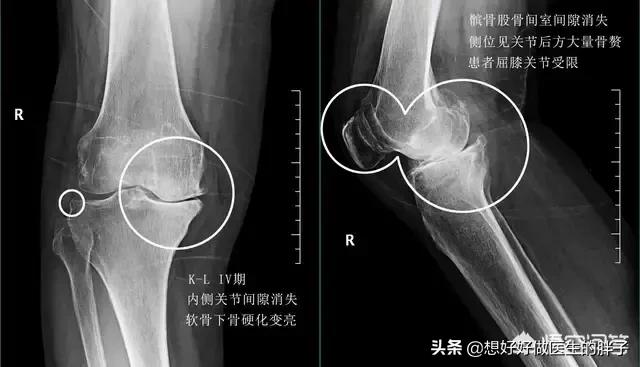

●晚期骨关节炎:患者到了骨关节炎的晚期,关节软骨磨损的会特别严重,有一些患者关节内的软骨,尤其是在负重区的软骨,已经磨损消失了。此时的患者往往疼痛会特别的严重,严重的患者即使不活动的时候也会出现疼痛,这种情况,我们称之为静息痛,而且有一部分会因为疼痛在夜间疼醒,我们称之为夜间痛,而且大部分的患者关节已经出现了严重的畸形,有很多患者被折磨得痛不欲生。